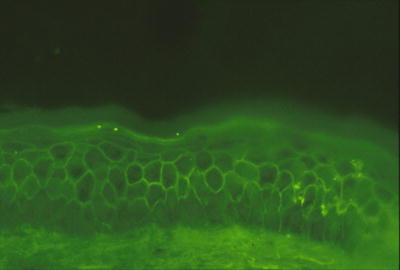

3.4.2 Histology

IgA pemphigus, likely identical to Sneddon–Wilkinson syndrome , has two predominant histologic patterns. In one pattern, neutrophils aggregate as subcorneal pustules, while in the other, they are deeper within the epidermis and accompanied by slight acantholysis [27]. Even less commonly, epidermal acanthosis resulting in a pattern resembling pemphigus vegetans has been reported [28]. Direct immunofluorescence examination reveals intercellular staining throughout the epidermis with anti-IgA antibodies (Fig. 3.10).

Fig. 3.10

Intercellular staining throughout the epidermis with anti-IgA antibodies characterizes IgA pemphigus